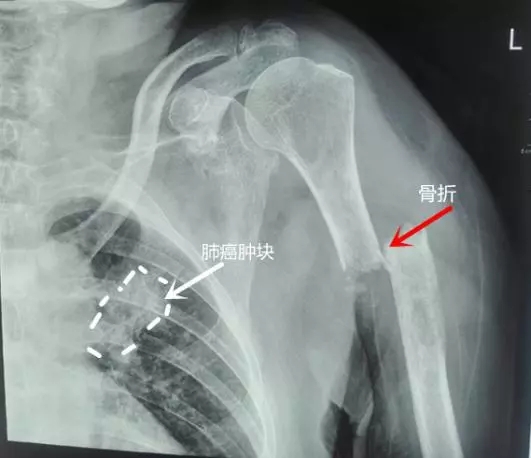

患者章奶奶今年74岁高龄,来捕鱼游戏 就诊后发现她的左肩膀剧烈疼痛,经捕鱼游戏 骨科初步检查发现章奶奶是晚期肺癌出现骨转移,左上臂肱骨出现了病理性骨折。(如图)。